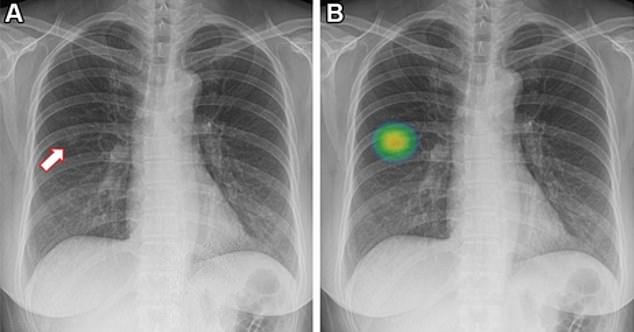

In a real-world setting, machine learning-based software significantly boosted the identification of lung nodules on chest X-rays.

The participants were randomly and evenly divided into two groups – AI or not-AI. The first group’s X-rays were analyzed by one of three radiologists using AI, while the second group’s were interpreted without the technology.

In 0.59 percent of cases, lung nodules requiring action were detected using AI — compared to 0.25 percent of the others whose images were reviewed only by radiologists.